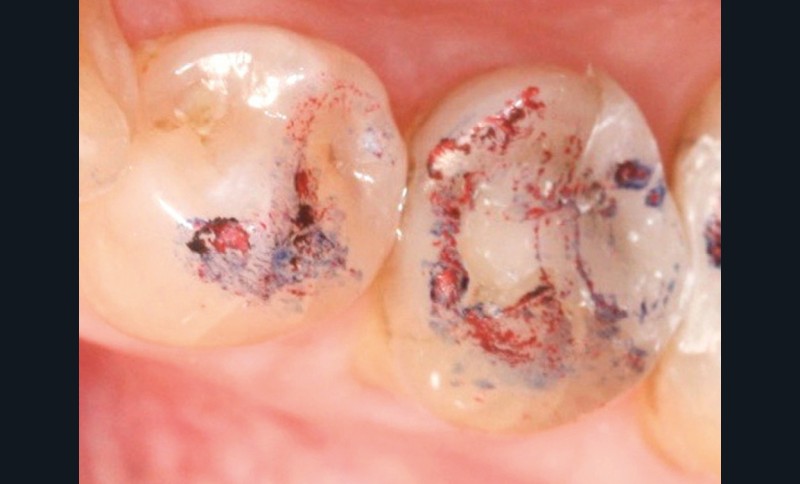

À chaque étape, le contrôle de l’occlusion est réalisé par technique du double marquage des points d’occlusion. Cette technique se base sur l’utilisation successive de deux marqueurs de teintes et d’épaisseurs différentes (40 µm et 8 µm). La superposition des marques permet de comparer et d’affiner l’analyse occlusale (fig. 1).